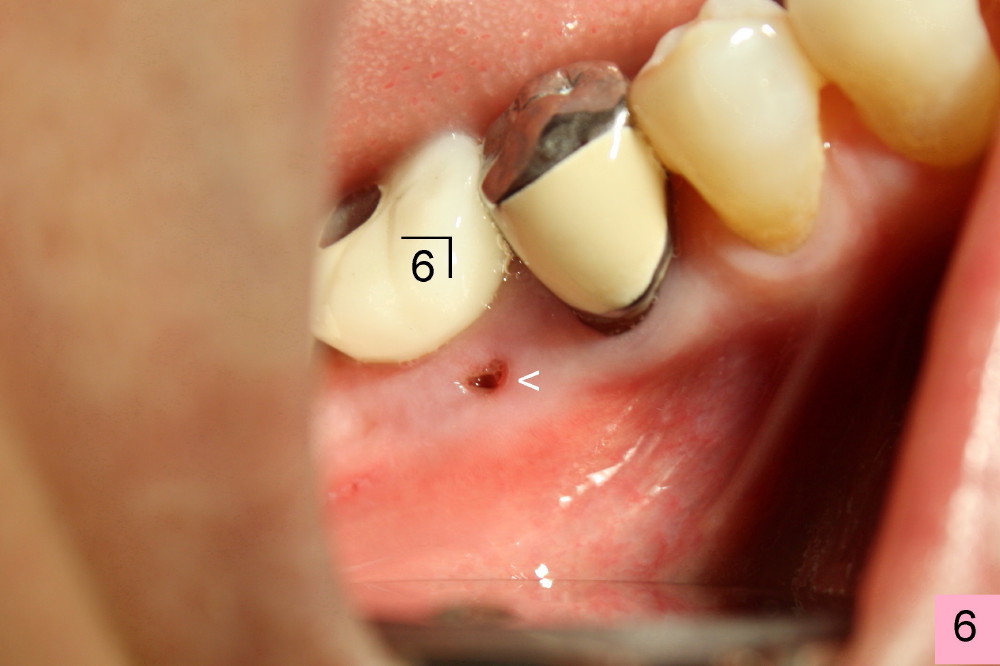

六十三岁台湾太太两年前右下第一磨牙准备做植牙,术前X光片显示缺牙区近中牙槽脊骨质好像有些特殊(图一箭头)。六乘十七毫米植牙(I)刚植入(图二,做了bone expansion),近中骨质好像又没有问题(箭头)。六个月后植牙近中骨质游离(图三箭头),除去骨片后,牙龈愈合,一个月后戴上牙冠(图四C),近中骨质仿佛没有异常。一年半后,病人突然回诊所,抱怨植牙周围流出臭味水,有些压痛。检查发现牙冠近中有个瘘道(图六箭头),下面好像有游离骨片,植牙牢靠,根尖片显示近中上部骨质稀疏(图五*),游离骨片(箭头)。翻开牙龈,除去相当大游离骨片,植牙粗糙面暴露(图七*,原有游离骨片所在地),除去炎性肉芽组织(+ +)后,植牙上部一两个螺纹暴露,箭头表示骨缺损边缘。反复用生理盐水冲洗,然后稀释四环素溶液冲洗,用探针和curet轻轻刮除植牙表面和螺纹菌斑,涂Straumann PrefGel,又用生理盐水冲洗,涂Endogain,植入Rocky Mountain Irradiated Allogenic Cancellous Bone and Marrow (图八*)。沐旭生医生认为植骨可能不管用,细菌很难清除,最好拔除植牙,植骨,然后再植牙。病人自己也意识到这个可能性,现在只有希望奇迹出现:缺损太大,不植骨身体可能无法修复。